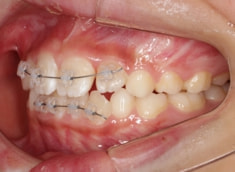

症例紹介

小児期ケース:叢生(ガタガタ)

治療法:拡大プレート+フルパッシブブラケット(クリアスナップ)

治療中